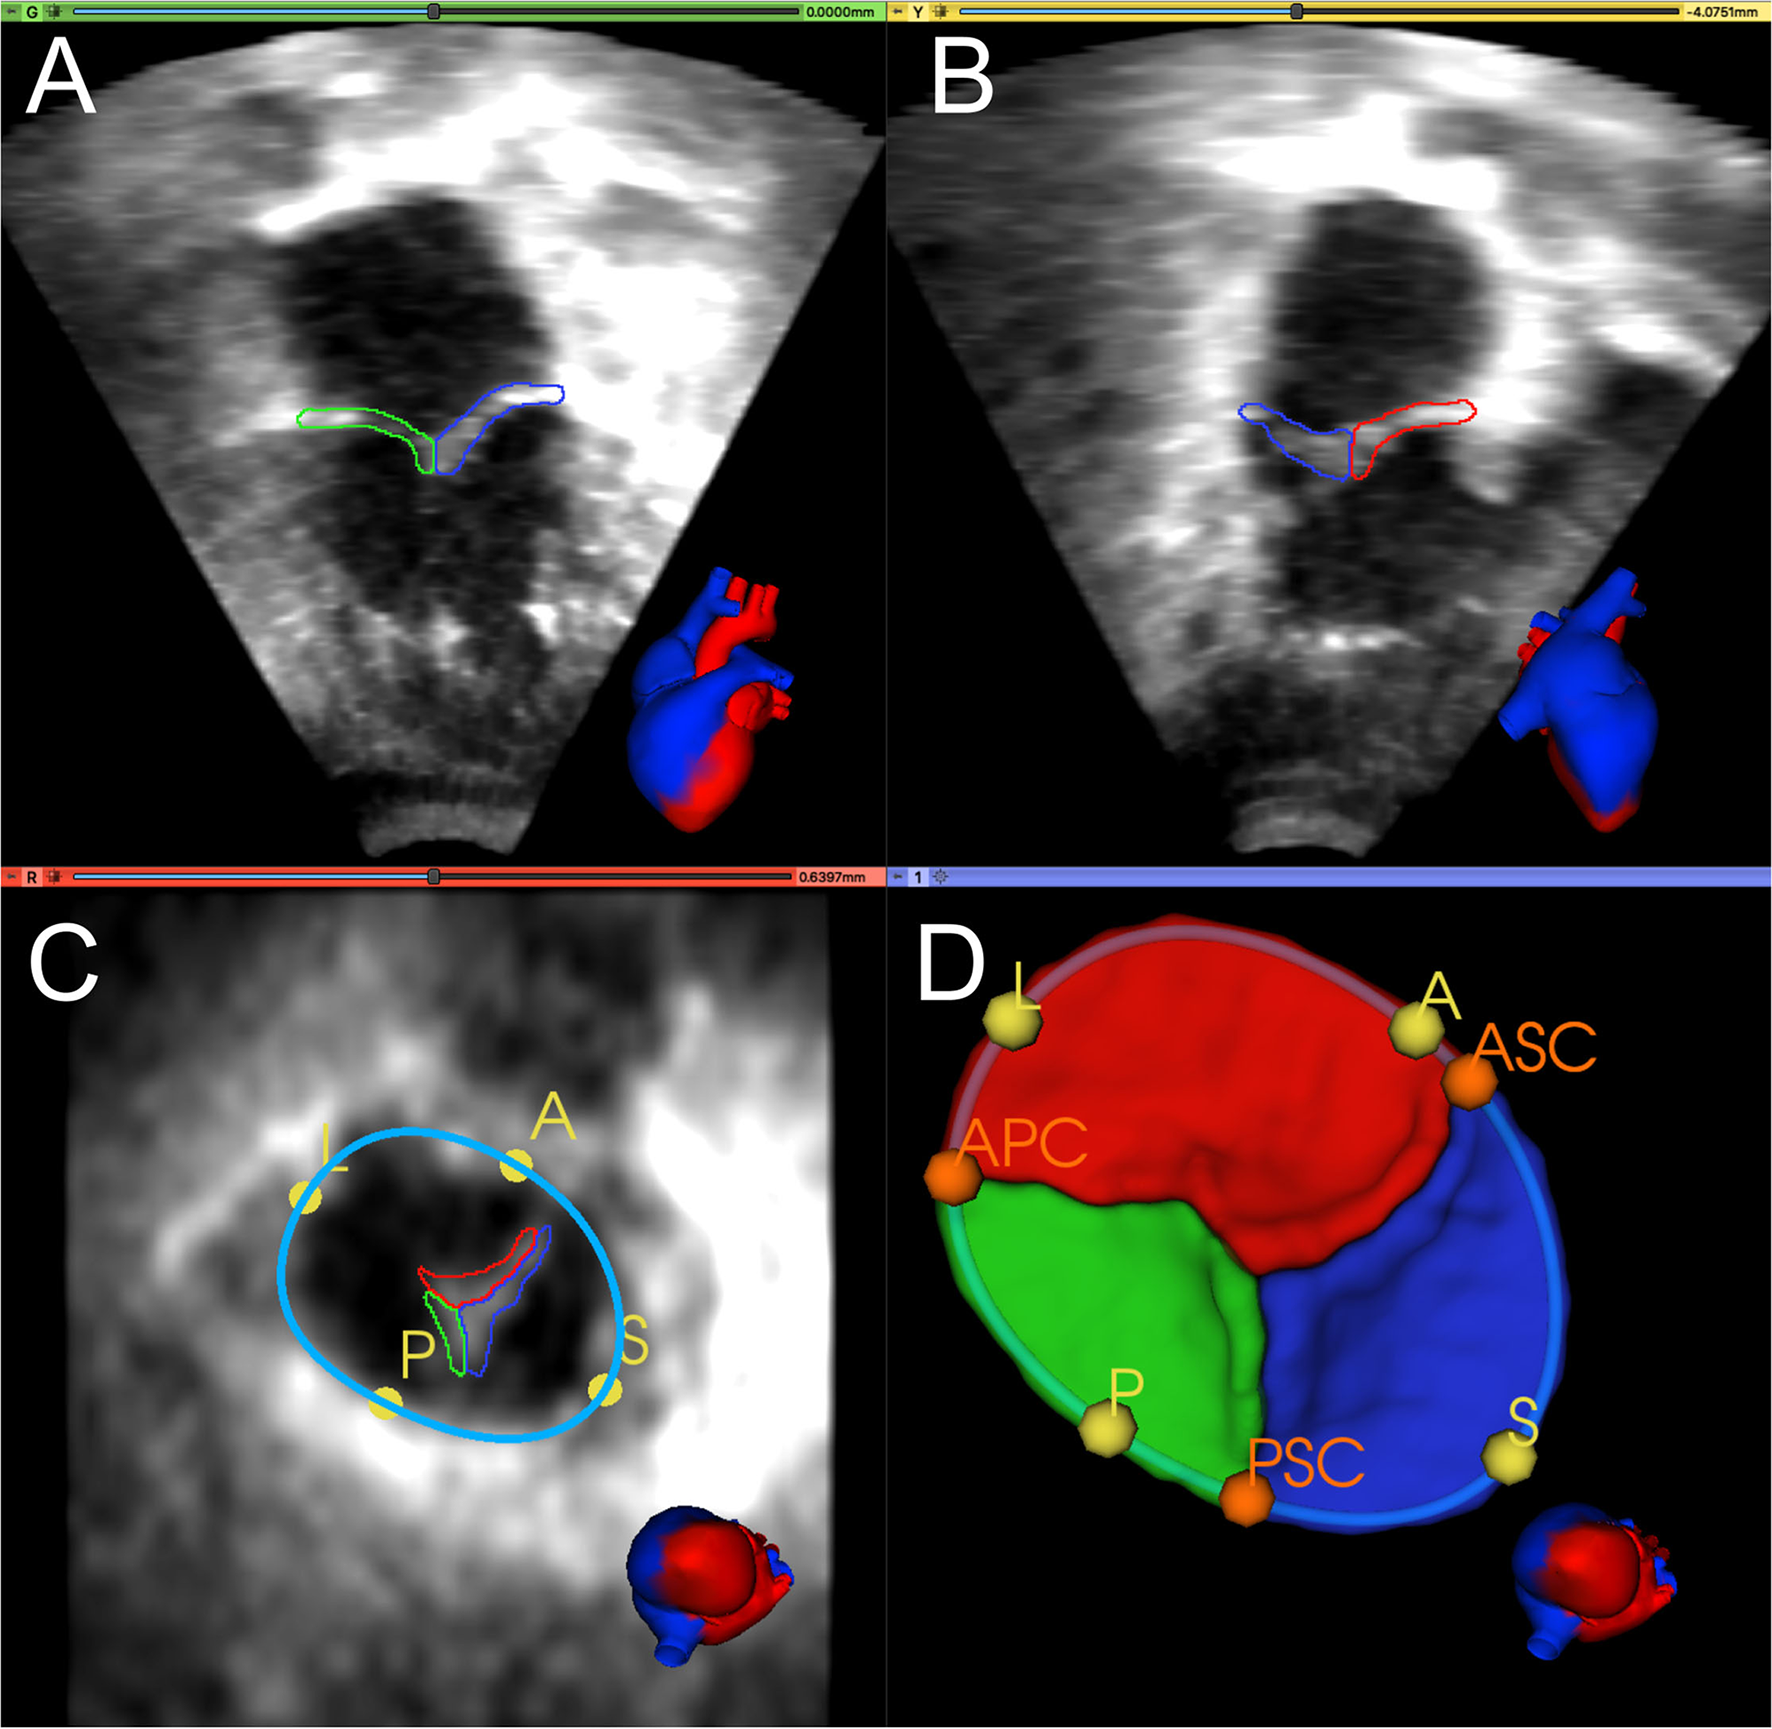

Figure 1 shows an example of TV segmentation and all annotated landmarks. First, an annular curve was manually created, as previously described (14). The annular curve creation takes an expert segmenter approximately thirty seconds for a rough curve and approximately two min for a high-precision curve. The three individual TV leaflets were manually segmented using the SegmentEditor module in 3D Slicer, followed by smoothing with a median filter and removal of any extraneous islands created by the manual process. Time for manual TV leaflet segmentation by an experienced segmenter varied from 2 to 4 h, depending on the complexity of the valve and quality of the image. Finally, the segmenter manually identified valve quadrant landmarks corresponding to the anterior, posterior, septal, and lateral regions (A, P, S, L) of the annulus, which took approximately 20 seconds. In addition, commissural landmarks (boundaries between the leaflets near the valve annulus) corresponding to the anterior-septal, posterior-septal, and anterior-posterior commissures (ASC, PSC, APC) were identified. These commissural landmarks were manually placed between individual leaflets by selecting points restricted to the annular curve. In this case, identification of the commissures was trivial as the leaflets had already been segmented. However, in de novo, unsegmented valve identification and point placement at the commissures takes approximately a minute if the annular curve has already been created, and several minutes without the guidance of an annular curve.

Figure 1. Manual segmentation and annotation of the tricuspid annulus and leaflets. (A) Apical 4-chamber view of 3D TTE MS frame showing the posterior (green) and septal (blue) leaflet; (B) Apical 2-chamber view of 3D TTE MS frame showing the anterior (red) and septal (blue) leaflet. (C) Ventricular view of 3D TTE MS frame with all three leaflets, the annular curve (light blue), and the quadrant landmarks (yellow): anterior (A), posterior (P), septal (S), and lateral (L). (D) 3D model of the segmented TV and the annular curve with APSL quadrant landmarks (yellow) and commissural landmarks (orange): anterior-septal commissure (ASC), posterior-septal commissure (PSC), and anterior-posterior commissure (APC). A heart avatar (red = left heart and aorta, blue = right heart, inferior and superior vena cava) is also provided for orientation of the echocardiographic views.